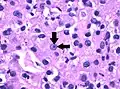

Generally, the cells have a clear cytoplasm, are surrounded by a distinct cell membrane and contain round and uniform nuclei.

Microscopically, CCRCCs are graded by the ISUP/WHO as follows:[1][2]

• Grade 1: Inconspicuous and basophilic nucleoli at magnification of 400 times

• Grade 2: Clearly visible and eosinophilic nucleoli at magnification of 400 times

• Grade 3: Clearly visible nucleoli at magnification of 100 times

• Grade 4: Extreme pleomorphism or rhabdoid and/or sarcomatoid morphology